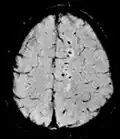

T2* Spoiled gradient recalled echo (GRE) with a long echo time and small flip angle[11] Low signal from hemosiderin deposits (pictured) and hemorrhages.[11]

Susceptibility-weighted SWI Spoiled gradient recalled echo (GRE), fully flow compensated, long echo time, combines phase image with magnitude image[12] Detecting small amounts of hemorrhage (diffuse axonal injury pictured) or calcium.[12]